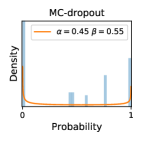

5.1 Distribution of Uncertainty Scores

Distribution of Uncertainty Scores Across Different Severity Levels As explained in Section 3, each uncertainty metric essentially defines an order/ranking among the data points. We conducted an analysis to better understand what data will be assigned high uncertainty under a particular uncertainty metric . Picking out the highest ranked data points (), we calculated the ratio of data points from each SL. Figure 4 summarizes the results as box plots for the Kaggle-DR and the Messidor-2 datasets; additional detailed statistics can be found in Table S.1 in the supplementary materials. From the plot and table, SL1 & SL2 examples account for a higher proportion among the top-ranked uncertain examples across the three ensemble methods. This finding matches our intuition that incipient disease examples (SL1 & SL2) are more likely to be considered uncertain by ensemble methods due to their ambiguity.

Comparing the three ensemble methods in Figure 4, the stacking ensemble method has the highest ratios of SL1 & SL2 data among the high-uncertainty examples it identified under both mean and var. TTA showed slightly better performance than MC-dropout but still falls behind the stacking ensemble method. Considering the fact that SL0 examples accounted for the majority of the dataset, the stacking ensemble method was much more precise (specific) in selecting truly ambiguous data points that were difficult to classify. From Figure 3, we can also see that the stacking ensemble method greatly outperformed the other two methods in finding false negatives under both mean and var uncertainty metrics.

In contrast, the MC-dropout method showed the worst overall performance among the three, as it can be seen from the high ratios of SL0 examples among the uncertain negatives in Figure 4. The histograms in Figure 2 provides another perspective to look into the phenomenon, where a decent proportion of MC-dropout model’s predictions on SL0 inputs entailed low confidence (far from 0 or 1), which from another angle explained why MC-dropout was less specific in terms of lower FNP; many no-DR inputs (i.e. SL0) were erroneously assigned high uncertainty by MC-dropout models.

It is still an open question why the evaluated MC-dropout networks signaled relatively high uncertainty on SL0 & SL3 & SL4 data that are less likely to be ambiguous. We conjecture that much of the “uncertainty” indicated by disagreement among test-time dropout samples actually reflects the stochastic nature of dropout networks rather than the real decision uncertainty associated with the data. It is worth noting that the MC-dropout model we evaluated was not weak per se; they all achieved above Area Under Curve (AUC) scores on test sets. The weakness of individual test-time samples (which explains their low-confidence predictions on SL0 & SL3 & SL4) might have been hidden when they are aggregated into an ensemble—a well-known advantage of ensemble learning. Our results suggested that the uncertainty information given by implicit ensemble methods such as MC-dropout and TTA might not be as reliable as that from explicit ensemble approaches (e.g., stacking ensembles). Similar findings on MC-dropout can be found in some previous papers [1].